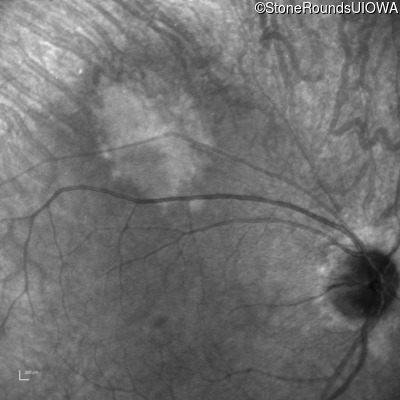

Infrared Fundus Photograph - Left - 20/32

Exemplar